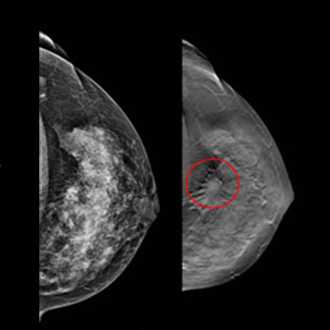

Mammography is important because in its earliest stages breast cancer may not be palpable; it may be too small to feel as a lump or tissue change. Mammography can help detect these changes two years or more before you would feel them. Physical examination is also important because premenopausal breast tissue is often dense and fibrous, which may decrease the reliability of mammography for young women.

Breast screening (mammography) is an X-ray examination of the breasts Breast screening can show breast cancer at an early stage, when they are too small for you or your doctor to see or feel

Breast screening can help find small changes in the best it shows up. Early detection of breast cancer offers the best chance of successful treatment, which significantly improves a woman’s chance of survival.